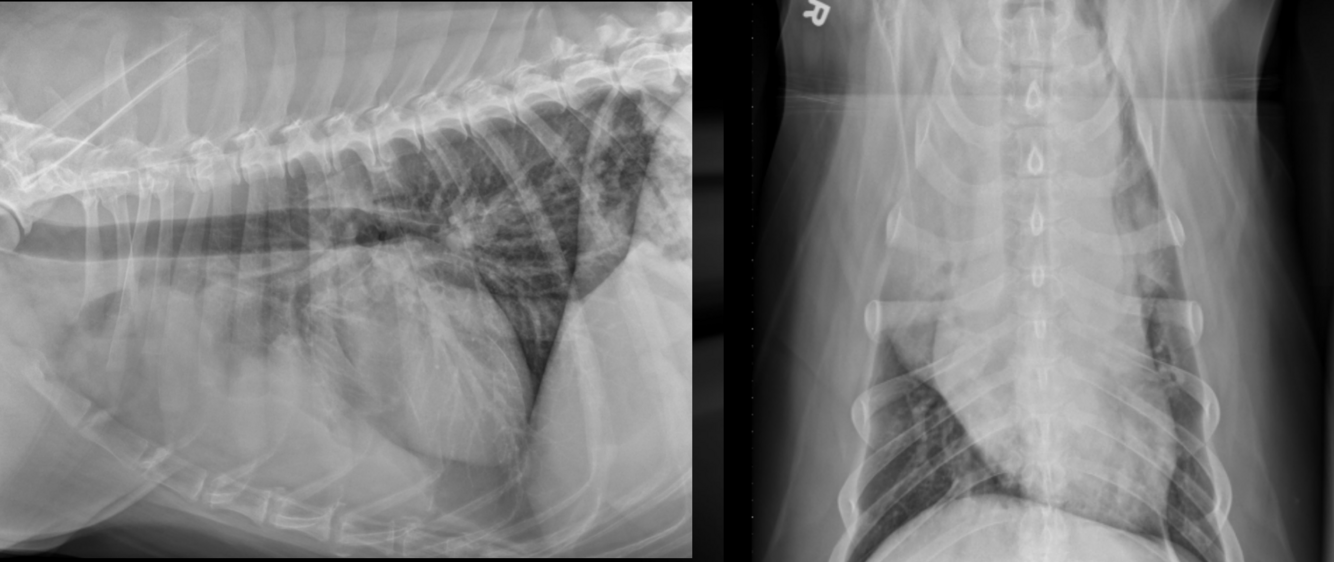

What is shown in these images?

generalized megaesophagus: -left: large bubble of esophagus -right: widened mediastinum

megaesophagus with aspiration pneumonia -gas-filled tube -thickened appearance of trachea -patchy alveolar patten in lungs